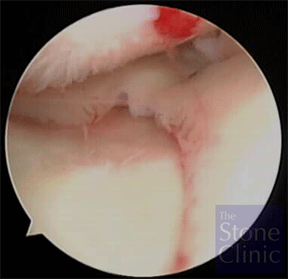

Microfracture was performed on an eburnated (lacking articular cartilage) area on the tibial plateau. The photo on the left shows the exposed bone where cartilage has been lost. The photo on the right shows the same area where microfracture is being performed by 'picking' through the surface to expose the bone marrow.